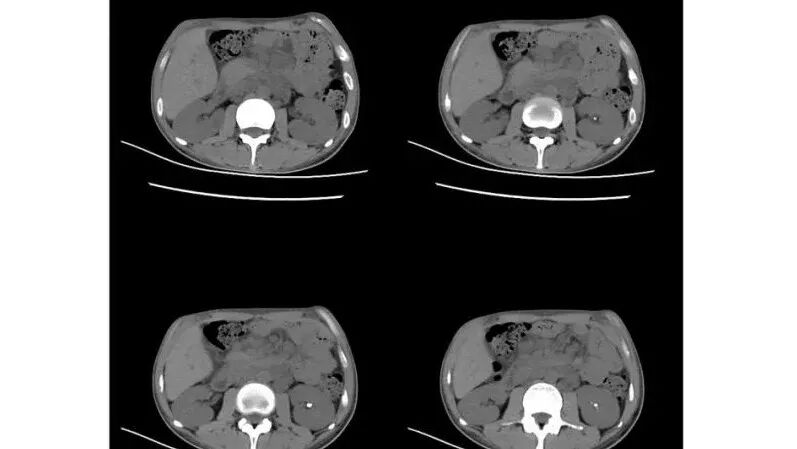

以下为2021-7-15日上腹部CT

影像与临床:1.青年男性,HlV阳性,颜面部皮疹(未提供皮疹图像)、发热(高热),实验室CRP、PCT高,T-Spot阴性。2.右肺下叶空洞结节,壁厚不均,边界清楚,其内线状影,未见液平及钙化,未见卫星灶,纵隔淋巴结增大,双侧腋窝见增大淋巴结。心腔内低密度提示贫血可能。肝脾影增大,未见结节影及块影。腹膜后见多发增大淋巴结。

综合分析:本例肺部影像学改变并不具有特征性,空洞性病灶须与多种疾病鉴别,但年轻HIV阳性患者,高热,皮疹,肝脾增大,纵隔、腋窝、腹膜后见多发增大淋巴结等都强烈提示马尔尼菲篮状菌感染的可能性。